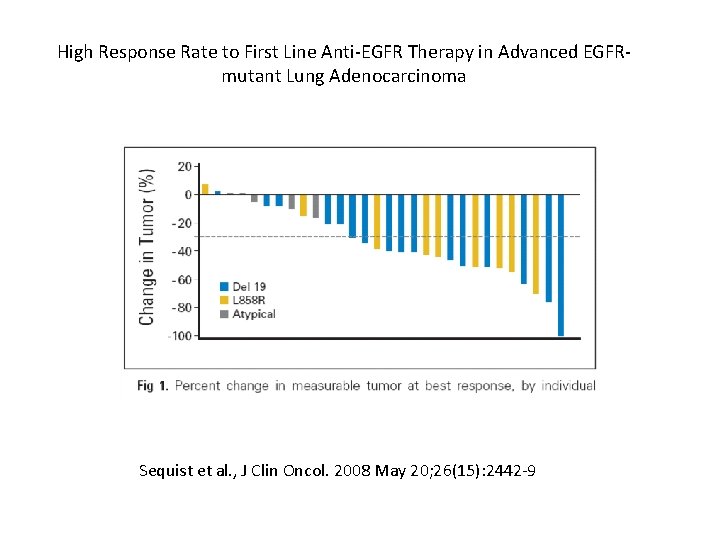

High Response Rate to First Line Anti-EGFR Therapy in Advanced EGFRmutant Lung Adenocarcinoma Sequist et al. , J Clin Oncol. 2008 May 20; 26(15): 2442 -9